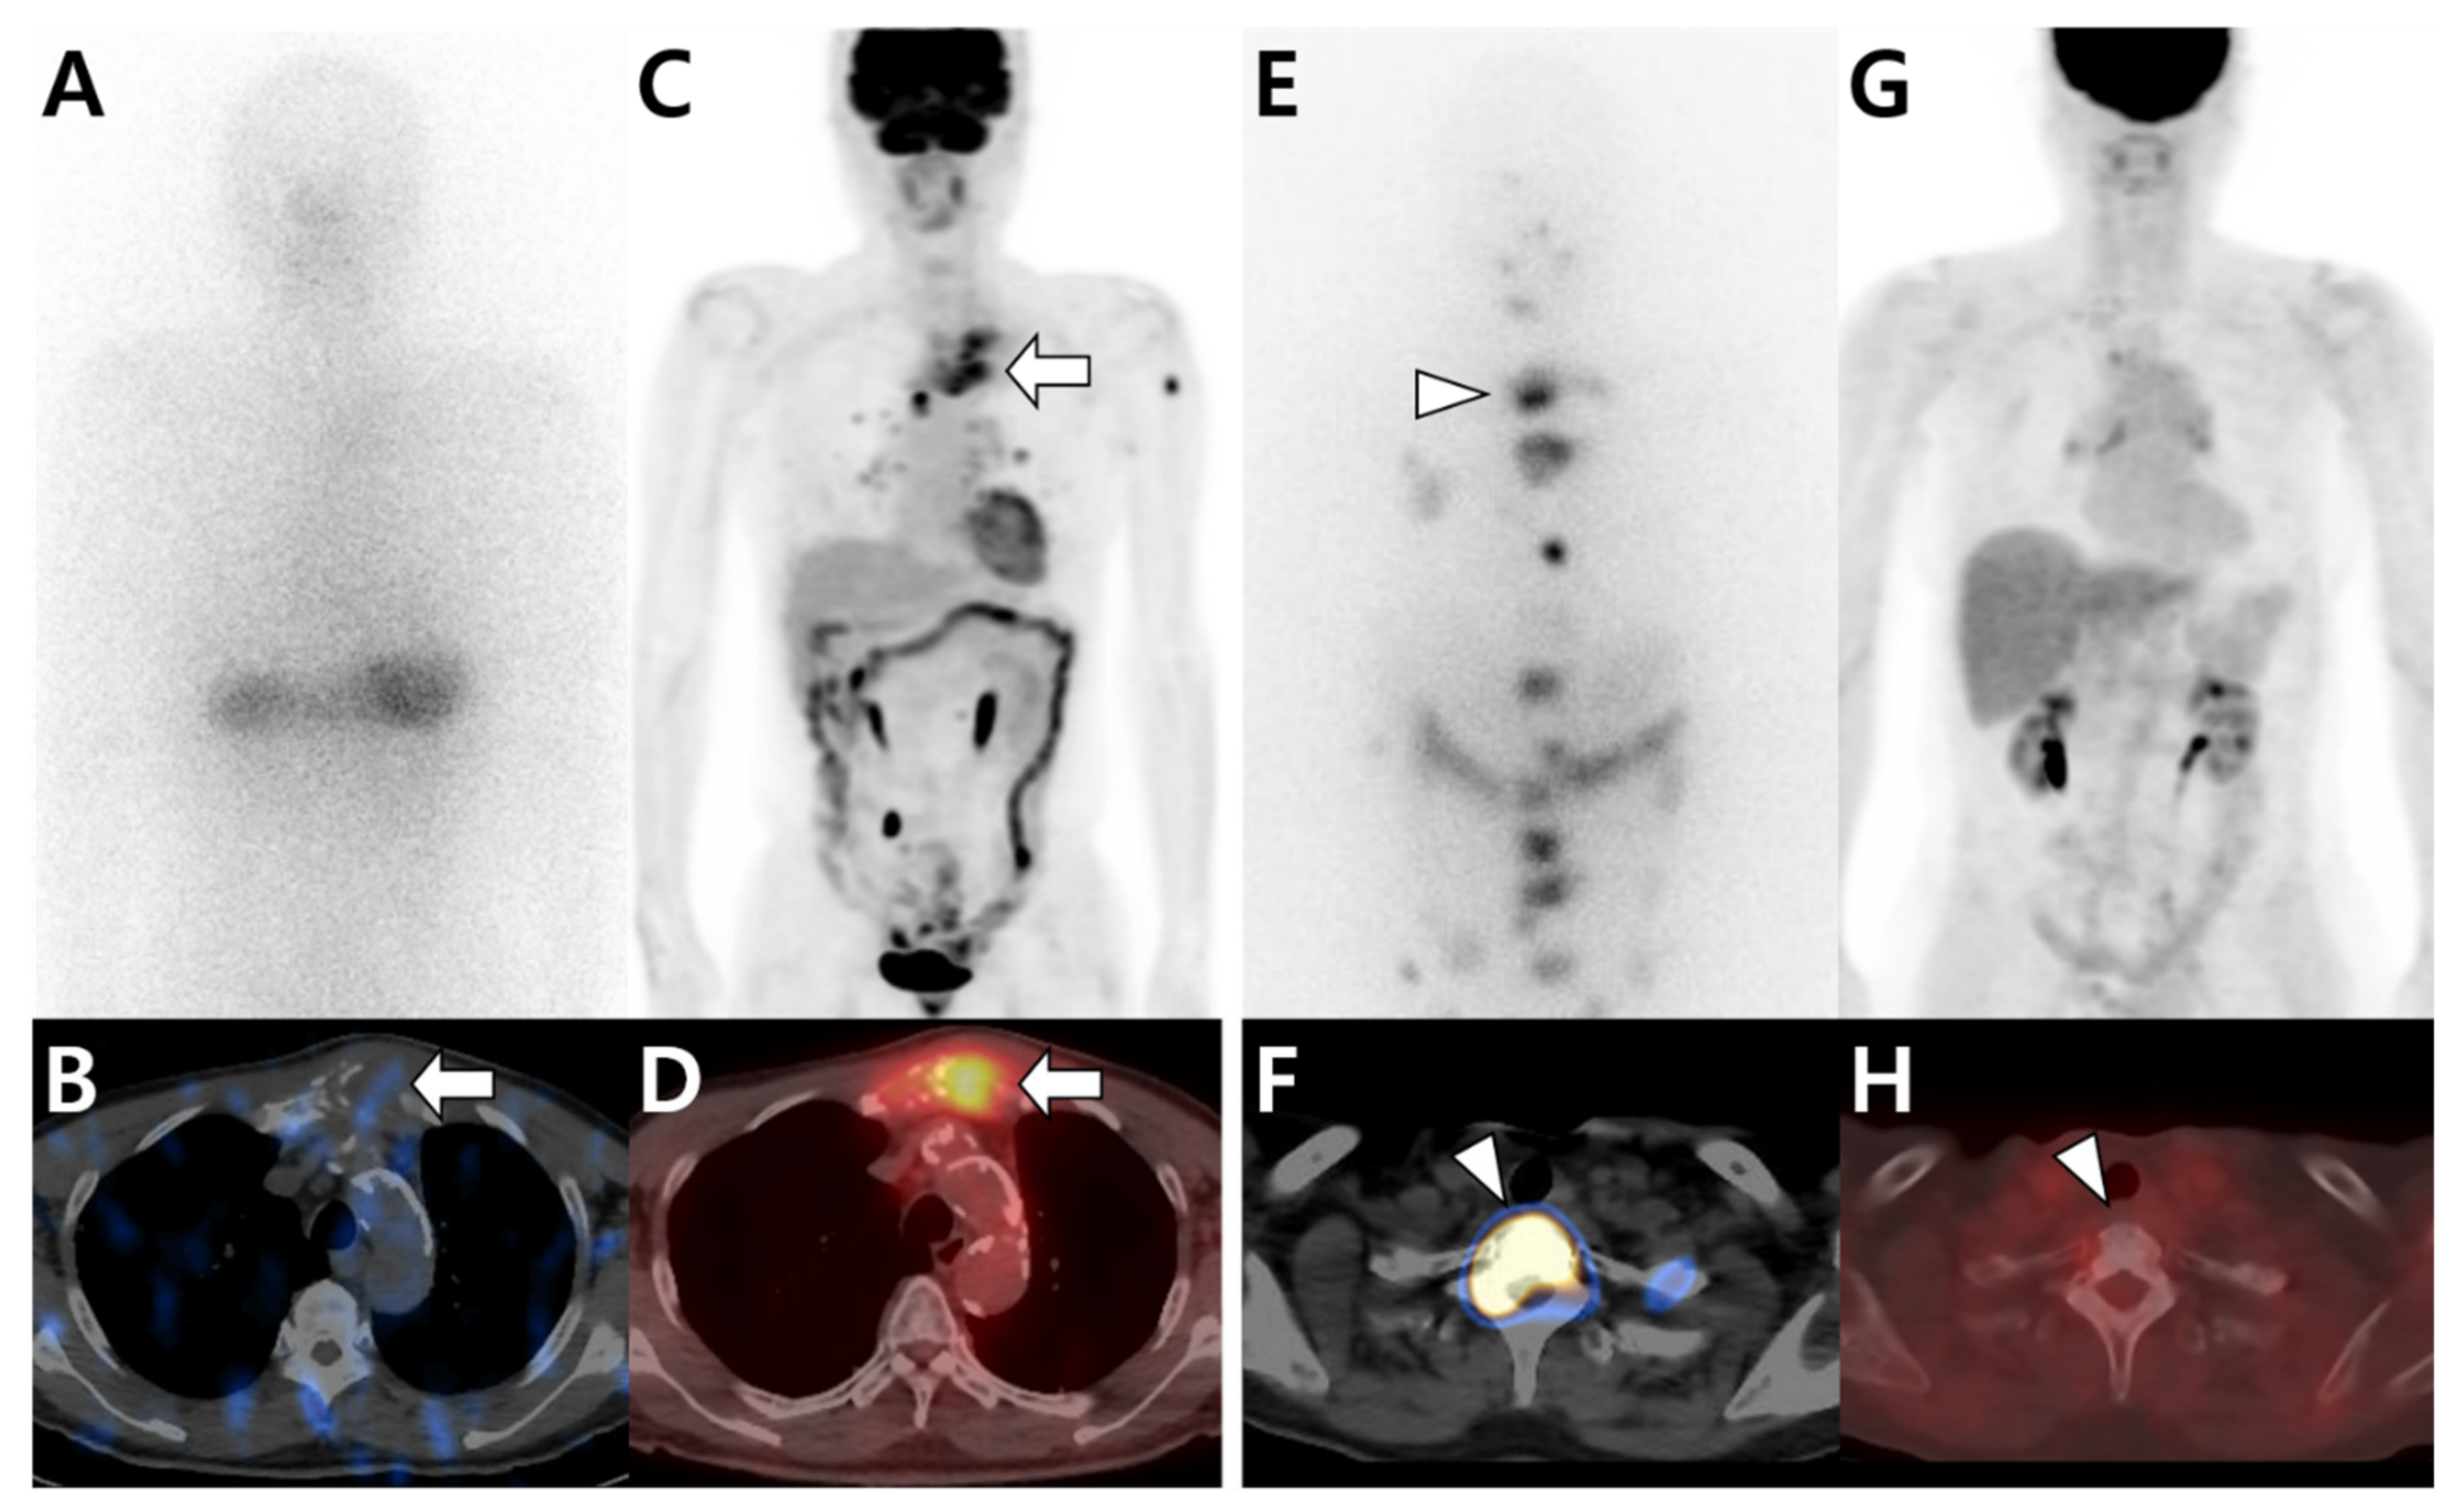

3.1. Multimodal Imaging According to the Primary Tumor Site and Histologic Type

3.2. Multimodal Imaging According to the Differentiation Status of the Primary Tumor